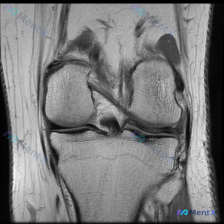

临床疑诊软骨异常但MRI仅见单冠状位T1像正常?这份分析值得看看

刚整理了一份很有代表性的膝关节影像病例,临床核心问题是询问「软骨异常」的影像学发现,分享一下我的分析思路。

核心问题:临床疑诊膝关节软骨异常,提供单张膝关节冠状位T1加权MRI影像供分析。

影像所见

- 骨骼结构:股骨远端、胫骨近端、腓骨近端骨皮质完整,无骨质破坏/断裂,股骨髁与胫骨平台关节面清晰,骨髓信号无异常水肿或局灶异常改变。

- 半月板:内、外侧半月板均为典型三角形低信号,形态完整边缘平滑,无异常高信号穿透关节面,结构连续。

- 韧带结构:交叉韧带走行自然,信号均匀低信号,无中断或水肿;内、外侧副韧带无明确信号增高或增厚。

- 关节与软组织:关节间隙宽度正常对称,无明显关节积液,髌下脂肪垫信号无异常,无骨赘增生,软骨下骨皮质边缘光整。

初步判断

基于目前可见影像范围:膝关节冠状位T1加权MRI未见明确结构性异常,也未发现支持「软骨异常」的明确影像学证据。